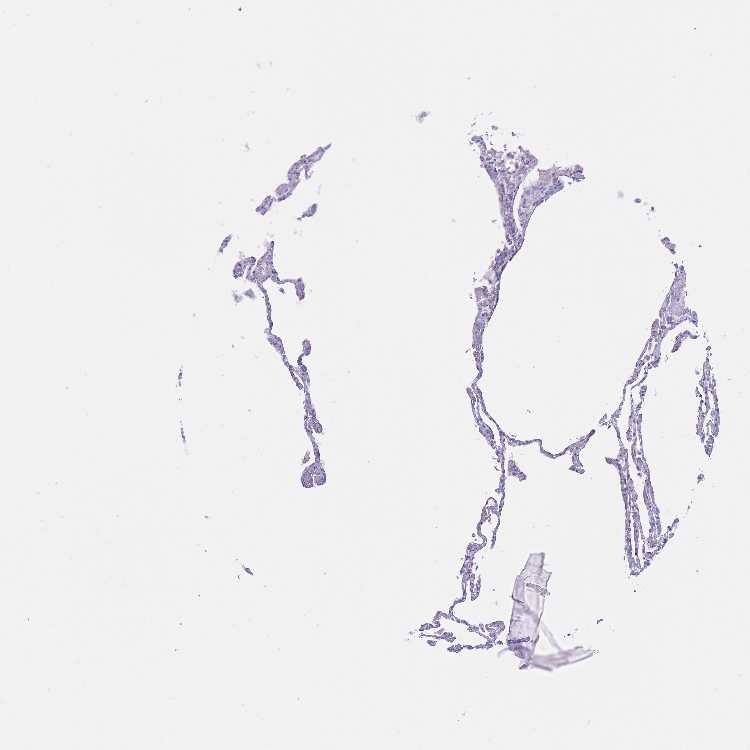

LUNG - Antibody stainingi

Antibody staining in the annotated cell types in the current human tissue is reported as not detected, low, medium, or high, based on conventional immunohistochemistry profiling in selected tissues. This score is based on the combination of the staining intensity and fraction of stained cells.

Each image is clickable and will lead to virtual microscopy that enables deeper exploration of all samples and also displays staining intensity scores, fraction scores and subcellular localization as well as patient and tissue information for each sample.

Antibody HPA050342

Alveolar cells Not detected

Macrophages Not detected